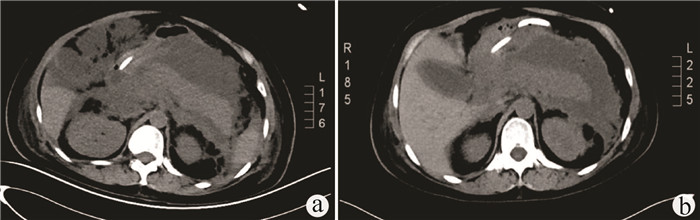

Hereditary hemorrhagic telangiectasia of the liver: A case report

Tingting WANG, Liang MA, Jianping CHEN

2022, 38(2): 423-425. DOI: 10.3969/j.issn.1001-5256.2022.02.032

Abstract(1009) HTML (348) PDF (2696KB)(39)

Abstract: